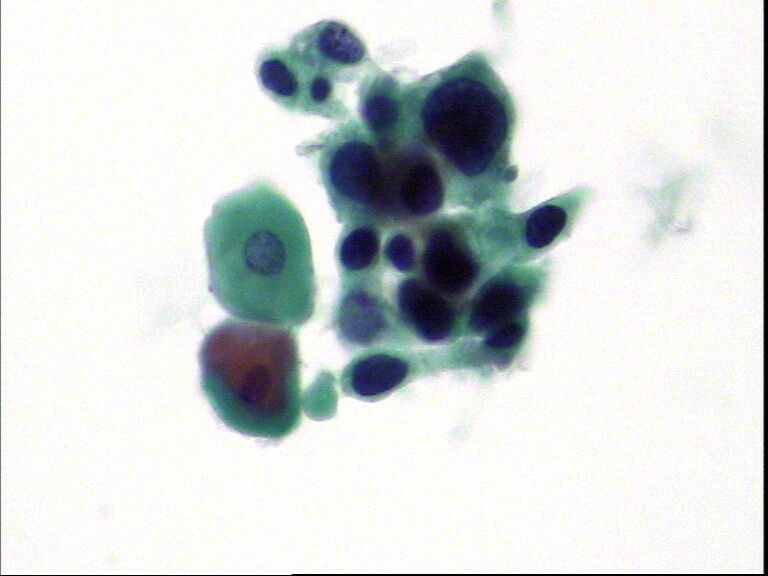

宫颈液基,老年妇女,78岁,临床:宫颈肥大

• 宫颈液基,老年妇女,78岁,临床:宫颈肥大图1

图1

HSIL,建议活检。

HSIL,疑SCC。

HSIL,不除外SCC建议活检。

宫颈高级别上皮内病变,不除外鳞状细胞癌(建议活检)。